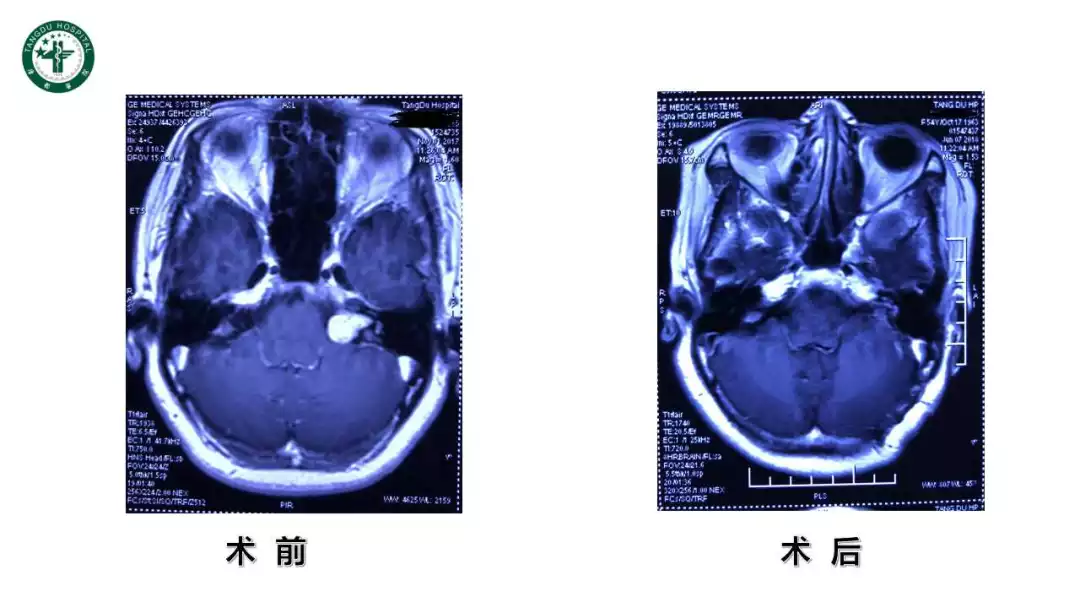

今日与大家分享的是《正海-妙术视界》第一百〇一期唐都医院神经外科主任屈延教授带来的精彩病例:“前庭神经鞘瘤面听功能保护体会”,欢迎观看、分享。

屈延教授:前庭神经鞘瘤面听功能保护体会